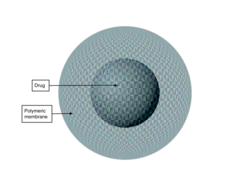

Polymer-based nanoparticles

Polymer-based nanoparticles can be made from either natural or synthetic sources. Nanospheres and nanocapsules are polymeric nanoparticle systems. Natural polymers can be found in the environment or human body. On the other hand, synthetic polymers do not occur naturally and are artificially developed polymers with chemical modifications. Natural polymer-based nanoparticles can be made up of chitosan, hyaluronic acid, alginate, and gelatin. Natural polymers exhibit excellent biocompatibility and biodegradability, and low toxicity. Synthetic polymer-based nanoparticles can consist of polyglycolic acid (PGA), poly (lactic acid) (PLA), and poly(lactide-co-glycolide) (PLGA).